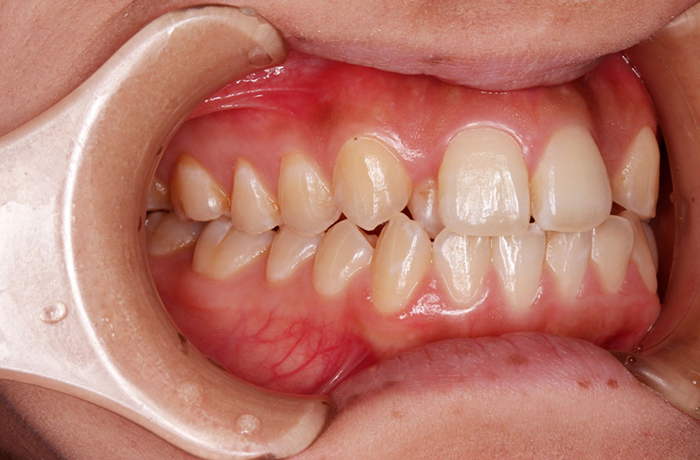

I様

治療前

before

年齢 34歳

性別 男性

治療名称 マウスピース型カスタムメイド矯正歯科装置(インビザライン)・コンプリヘンシブパッケージ(フルパッケージ)

総額治療費用 770,000円(税込) 金額備考 検査・診断料33,000円含む

治療期間 8か月 通院頻度など 40日ごと

その他治療に関する情報 1枚につき10日装着を指示しました。

患者の症状 上顎前歯の凸凹

治療方法 非抜歯で、マウスピース型カスタムメイド矯正歯科装置による矯正

治療結果 歯並び、咬み合わせが良くなりました。

その他治療に関する情報 歯並びをより良くするために追加でアライナーを発注しました。

リスク/副作用 スペース不足を解消するために歯と歯の間をわずかに削合しました。